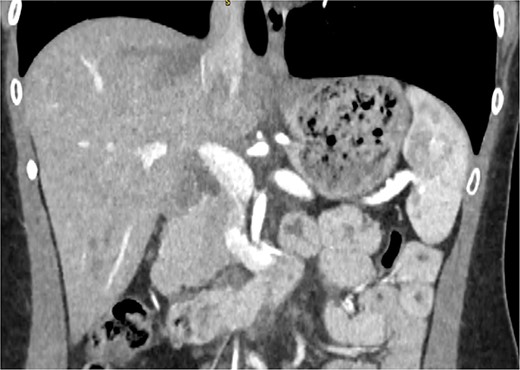

CT pancreas demonstrating absent body and tail of pancreas in coronal view.

A 29-year-old female, with a past medical history of asthma and anxiety, presented to A&E Department at Mater Dei Hospital in view of a 2-day history of worsening right-sided colicky flank pain that radiated down to the right iliac fossa. Pain relief, including paracetamol and NSAIDS, alleviated her symptoms temporarily; however, pain recurred after a few hours. At A&E, patient’s parameters were noted to be stable throughout the review. On examination, the patient’s abdomen was noted to be soft with tenderness over the right flank. No guarding was noted, and renal punch was negative bilaterally. Blood investigations were all within normal limits, and urinalysis was normal. In view of the examination findings, a computed tomography (CT) of the kidney, ureters, and bladder was ordered, which noted an enlarged pancreatic head measuring 3 cm in diameter with noted upstream atrophic changes in the body and tail with fat stranding; prominent mesenteric lymph nodes were also noted. Based on the previous CT findings, a contrast CT of the pancreas was ordered, which revealed that the body and tail of the pancreas were absent; however, the pancreatic head was noted to be enlarged. This can be seen in Figs 1 and 2. Prominent lymph nodes with ground glass changes in the mesenteric fat were noted. CT pancreas therefore confirmed the diagnosis of dorsal agenesis of the pancreas. The patient was discharged home on pain relief and an outpatient’s appointment with the hepatobiliary team. Upon review at outpatients, the patient was well. She noted that she had been complaining of intermittent right loin pain over the past 3 years. Over the 2 months from review at A&E, the patient was well and denied further abdominal pain. In view of this, the patient was reassured and discharged. She was advised to seek medical advice should symptoms recur.